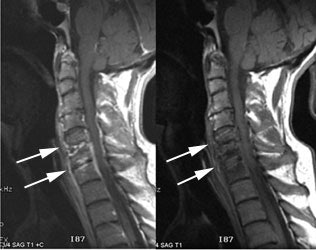

Cervical spine discitis and osteomyelitis: The case below is an example of the decreased sensitivity of In-111 WBC imaging for spinal infection. The MR images show abnormal disc enhancement at the C6-7 level consistent with discitis and enhancement of the C7 vertebral body consistent with osteomyelitis (white arrows). Post-gadolinium images are on the left. An In-111 WBC and Tc99m-Sulfur colloid exam in the same patient demonstrates a photopenic defect (black arrows) corresponding to the area of infection confirmed on the MR exam (white blood cell images are on the left). A defect on Tc-sulfur colloid imaging is seen with osseous infection due to marrow infiltration with inflammatory cells and edema which obstructs small arterioles. Click images to enlarge. |